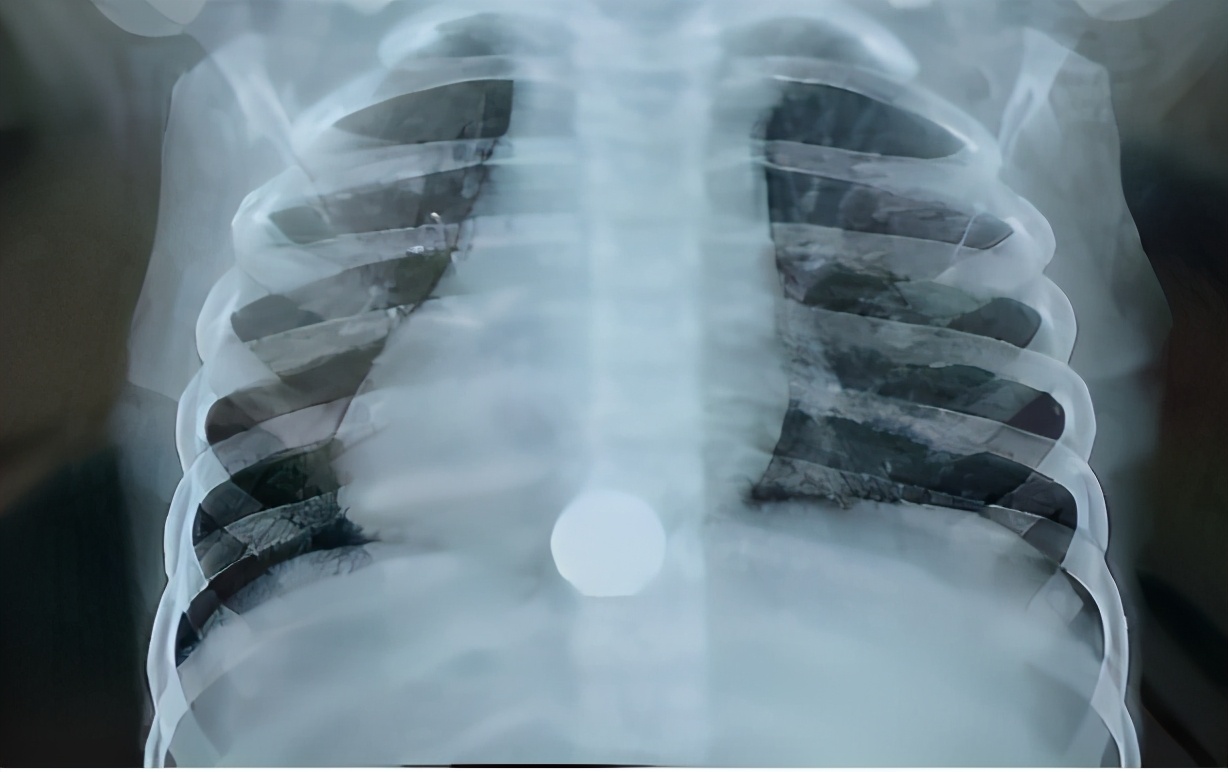

去到医院以后,急诊医生很快给他做了一个x光胸片检查。发现硬币就卡在食道下端,并没进入到胃。如前面所说,倘若这枚小硬币卡在食道下端和胃入口(贲门)交界狭窄处,就有可能因肌肉痉挛导致食道下端或者胃入口处出血,甚至撕裂性损伤及穿孔,所以应该尽早取出硬币。( 及时就医很重要)

孩子妈妈拿到这张x光胸片,即刻通过微信发到我的手机上,也就是图上所示的这张胸片,说急诊医生已经通知让住院手术,之前要进行一系列的前期准备并签署一些同意书之类的文件。孩子妈妈问我下一步怎么办?我告诉她应该遵从医生的意见,赶快签字做手术,但最终决定由自己做。随后不久,家长打来电话表示感谢,说硬币已经顺利被取了出来,心头一块石头终于落地。 (专业的事情交给专业的人做)